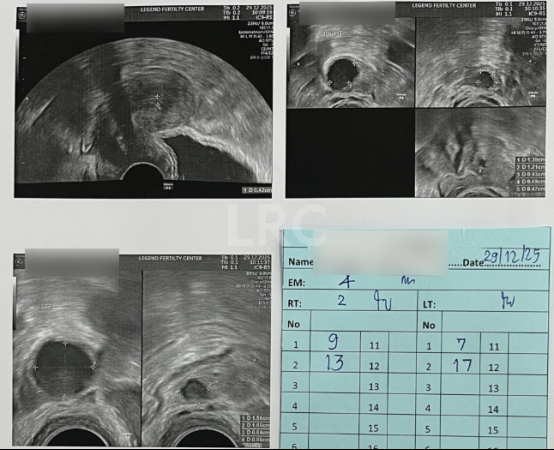

促排第六天

阴超检查:

- 右侧卵泡 2 颗 (13,9mm)

- 左侧卵泡 2 颗 (17,7mm)

激素水平检查:

- 促黄体生成素 12.30 miu/ml

子宫内膜厚度:4mm